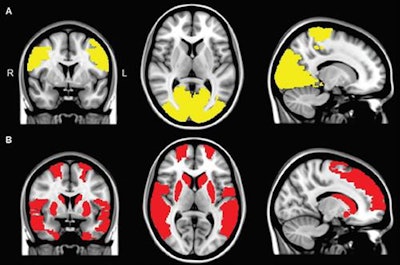

In addition, Parkinson's patients with visual hallucinations had reduced functional connectivity compared with the control subjects in nine brain regions. The underperforming regions were in the frontal cortex, temporal cortex, rolandic operculum, occipital cortex, and striatum and were related to cognitive deficits.

The regional connectivity analysis showed eight regions in the occipital lobe and paracentral area where functional connectivity was less for both Parkinson's patients with and without visual hallucinations, compared with the control participants. These regions are associated with motor performance.